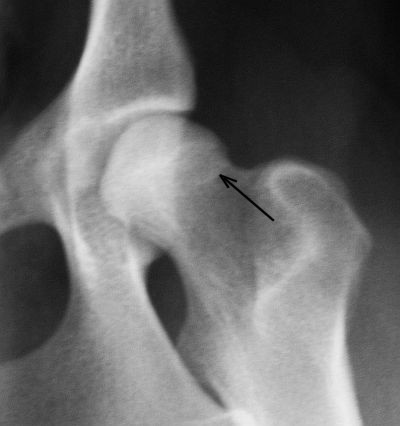

Dog is dysplastic with Severe HD

revealing a very shallow

acetabulum on dog's right side,

with thickening and flattening of femoral head and neck on this

dogs right side. The dog's

left side shows a severely

discintegratedsocket /femoral

head & neck with left hip

free floating, with the femoral

head being completely eroded away from damage..